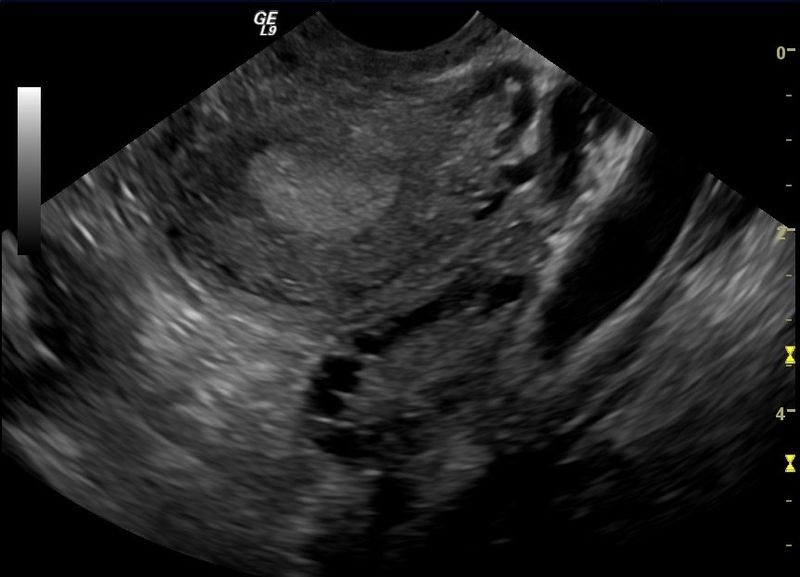

Typical ultrasound findings are numerous peripheral ovarian follicles (“cysts”), and/or ­ovarian volume >10cm3.

Fig 2 - Transvaginal scan of polycystic ovary.

Fig 2

Transvaginal scan of polycystic ovary.